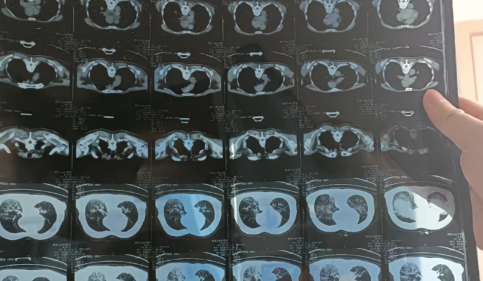

新冠白肺是比价常见的一个症状,现在无论老人还是年轻人如果新冠感染一直咳又不康复的话,可能会出现白肺或者肺炎的情况。那么,新冠白肺可逆吗?84岁老人肺全白有救吗?一起来看看趣丁网带来的详细介绍吧!

新冠白肺是不可逆的,白肺患者的肺组织会发生几乎不可逆的肺纤维化、肺功能损伤。白肺是不可以也不会自愈的,如果不对白肺进行及时干预治疗的话,可能会导致人体无法正常进行呼吸和气血交换氧气,严重的话会危及生命。

同济大学附属上海市肺科医院呼吸监护室副主任医师张黎表示:重症的白肺患者,死亡率超过40%以上。虽然有部分患者可以治愈,但是肺部难以恢复到原来的健康状态,绝大多数患者会留下肺部纤维化的后遗症。